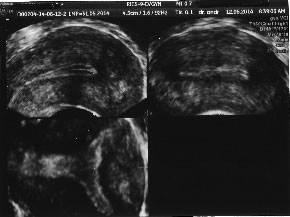

![]() | ![]() |

| Uter unicorn. Arhiva personala Dr. Lara Andronescu | Uter unicorn. Arhiva personala Dr. Lara Andronescu |